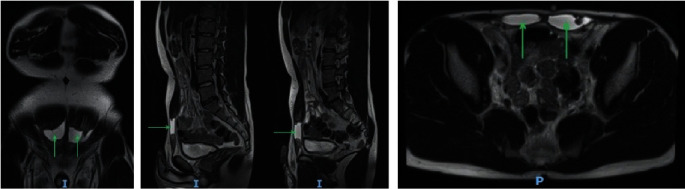

Rupture of the rectus abdominis is a rare condition. We describe the case of a young male trainee paratrooper who presented with sudden onset severe lower abdominal pain that occurred during military training. Magnetic resonance imaging revealed full-thickness bilateral rupture of the rectus abdominis. Our management involved injecting botulinum toxin into the rectus muscles preoperatively, reconstructing the rectus muscles, and placing a supportive biosynthetic mesh. Postoperatively, our patient could walk pain-free at 3 weeks, jog pain-free at 10 weeks, and run up to 2 miles at 25 weeks. As there is no consensus on the management of this rare injury, we conducted a literature review on all cases reporting rupture of the rectus abdominis from the year 2000. After comparing the outcomes of conservatively versus surgically managed patients, we can conclude that generally, management of such defects is dependent on size, severity, and patient factors; however, surgical treatment yields comparable results to conservative treatment.